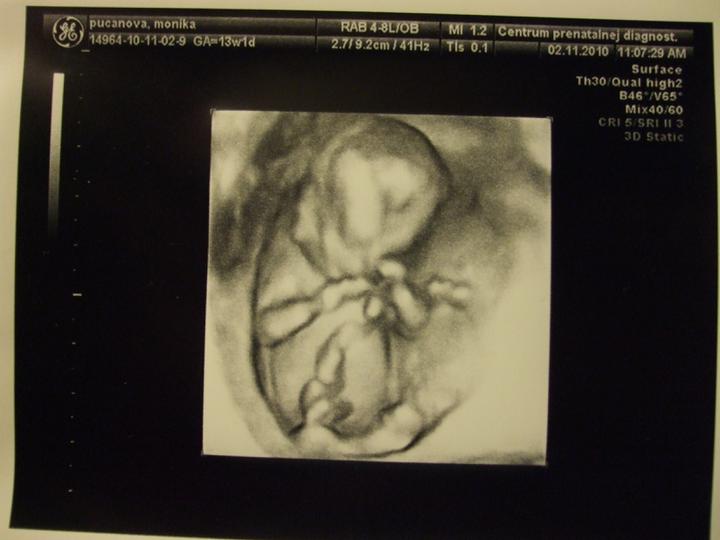

Prvá poradňa dopadla výborne, všetko je ok, malé rastie, srdiečko bije a vrtí sa jedna radosť 🙂